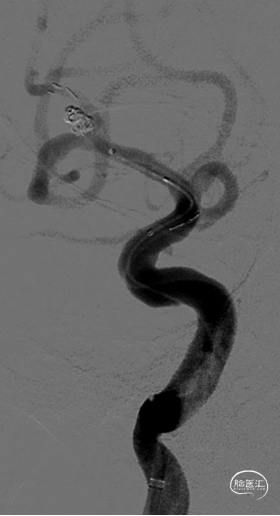

采取半释放法于上干释放3*21mm Altas支架1枚,同时于动脉瘤内填塞弹簧圈至致密。

最后全释放支架,序贯撤出微导管,造影可见支架打开完全、贴壁完美,载瘤动脉角度变化小,管腔通畅,动脉瘤Raymond 1级栓塞。

Atlas支架开环设计,血管直径跨度大时支架贴壁性能好,顺应血管走形轴向柔顺性好,并且输送导管细利于超选择插管,释放顺滑定位准确,术后支架展示对血管影响细微,非常适合此类病例使用。